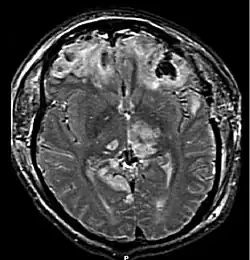

Numerous small contusions from broken capillaries that occur in grey matter under the cortex are called multiple petechial hemorrhages or multifocal hemorrhagic contusion.[14] Caused by shearing injuries at the time of impact, these contusions occur especially at the junction between grey and white matter and in the upper brain stem, basal ganglia, thalamus and areas near the third ventricle.[14] The hemorrhages can occur as the result of brain herniation, which can cause arteries to tear and bleed.[14] A type of diffuse brain injury, multiple petechial hemorrhages are not always visible using current imaging techniques like CT and MRI scans. This may be the case even if the injury is quite severe, though these may show up days after the injury.[15] Hemorrhages may be larger than in normal contusions if the injury is quite severe. This type of injury has a poor prognosis if the patient is comatose, even with no apparent causes for the coma.[15]